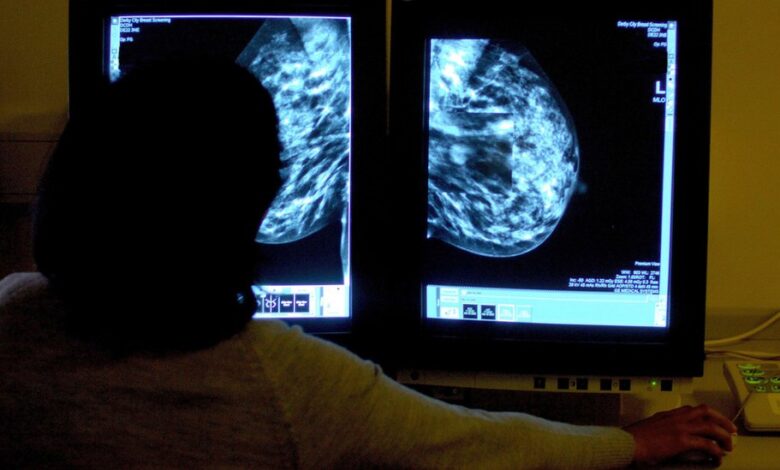

En este contexto, la detección temprana resulta crucial. La doctora Florencia Dri, especialista universitaria en Diagnóstico por Imágenes (UBA) y acreditada en Imagenología Mamaria (SAR, SAM), quien atiende en la Clínica de Diagnóstico San Nicolás y en el CINym, explicó a COSA CIERTA que “la mamografía digital es el método recomendado para detectar lesiones en etapas iniciales, incluso antes de que sean palpables”.

Gracias a este estudio, es posible identificar microcalcificaciones o pequeños tumores en fases tempranas, lo que aumenta significativamente las chances de cura y permite tratamientos menos invasivos.

Durante la mamografía, la paciente se coloca frente a un equipo especializado que comprime las mamas entre placas plásticas para obtener imágenes nítidas.

El procedimiento dura alrededor de diez minutos y suele ser indoloro; puede causar molestias leves que desaparecen rápidamente. Se recomienda asistir con ropa cómoda y sin objetos metálicos que interfieran con la toma de imágenes.

La ecografía mamaria complementa a la mamografía, especialmente en mujeres jóvenes o con mamas densas. Si bien esta técnica, que utiliza ondas ultrasónicas, es útil para evaluar lesiones sólidas o quistes benignos, no reemplaza a la mamografía en la detección precoz del cáncer debido a su menor sensibilidad para identificar microcalcificaciones.